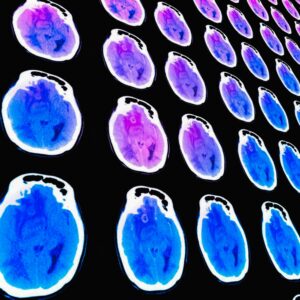

Η έναρξη των εργασιών, την Παρασκευή 24 Απριλίου (ώρες 18.00-20.00) περιλαμβάνει ειδικά διαμορφωμένες συνεδρίες για το κοινό, με στόχο την ενημέρωση και ευαισθητοποίηση γύρω από την πρόληψη των καρδιαγγειακών νοσημάτων. Καταξιωμένοι επιστήμονες θα αναπτύξουν σύγχρονες προσεγγίσεις για την έγκαιρη διάγνωση και πρόληψη, καθώς και τον καθοριστικό ρόλο της άσκησης και της διατροφής στη διατήρηση της καρδιαγγειακής υγείας. Ιδιαίτερη έμφαση θα δοθεί επίσης στη διεπιστημονική προσέγγιση, με θεματικές που συνδέουν την καρδιά με την άνοια, τον εμβολιασμό και τη σύγχρονη αντιμετώπιση της παχυσαρκίας.

Το επιστημονικό πρόγραμμα του Σαββάτου 25 Απριλίου 2026επικεντρώνεται στις νεότερες εξελίξεις στη σύγχρονη καρδιολογία σε αλληλεπίδραση με την παθολογία. Εξειδικευμένες συνεδρίες θα καλύψουν κρίσιμα ζητήματα, όπως η σύγχρονη διαχείριση της καρδιακής ανεπάρκειας και των συνοσηροτήτων της, η αλληλεπίδραση της καρδιάς με τις λοιμώξεις, καθώς και οι προκλήσεις στη χορήγηση αντιπηκτικής και αντιαιμοπεταλιακής αγωγής.

Ιδιαίτερο ενδιαφέρον παρουσιάζουν οι ενότητες που αναδεικνύουν τη σημασία της ολιστικής προσέγγισης στη σύγχρονη ιατρική πράξη. Η παχυσαρκία και το μεταβολικό σύνδρομο προσεγγίζονται ως σημαντικοί παράγοντες καρδιαγγειακού κινδύνου, με αναφορά σε καινοτόμες φαρμακευτικές θεραπείες αλλά και σε παρεμβάσεις στον τρόπο ζωής. Παράλληλα, η αναδυόμενη επιστημονική περιοχή της καρδιο-ογκολογίας αναδεικνύει την ανάγκη συνεργασίας μεταξύ ειδικοτήτων για την πρόληψη και διαχείριση της καρδιοτοξικότητας των αντικαρκινικών θεραπειών.